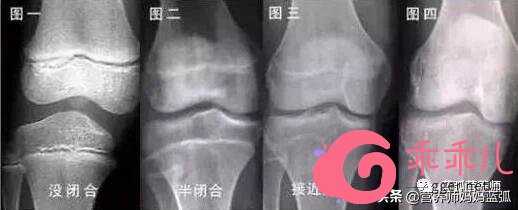

《应用心理学期刊》的一篇调查显示:销售员的身高比平均水平每多出一英寸,每年的收入就多出了789美元……说明身高在一定程度上会影响收入,身高还会影响人对能力和颜值的判断,不管一个人能力和颜值如何,如果身高有优势,就会自然给人“高人一等”的感觉。长高的“努力”一定要在骨骺线未完全闭合之前,骨骺线闭合后,长骨就不会再长长了,也就不会再长高了,所以成年人苦心求长高各种寻“增高秘方”,是没有意义的,只有发育期的孩子才有用。

骨骺线的闭合时间大概在21、22岁左右,当然个别体质差异会有不同,大多18岁以后就很难再长了,所以,一定要在可以努力的年龄去争取,不要等到成年再后悔哀叹空留遗憾。